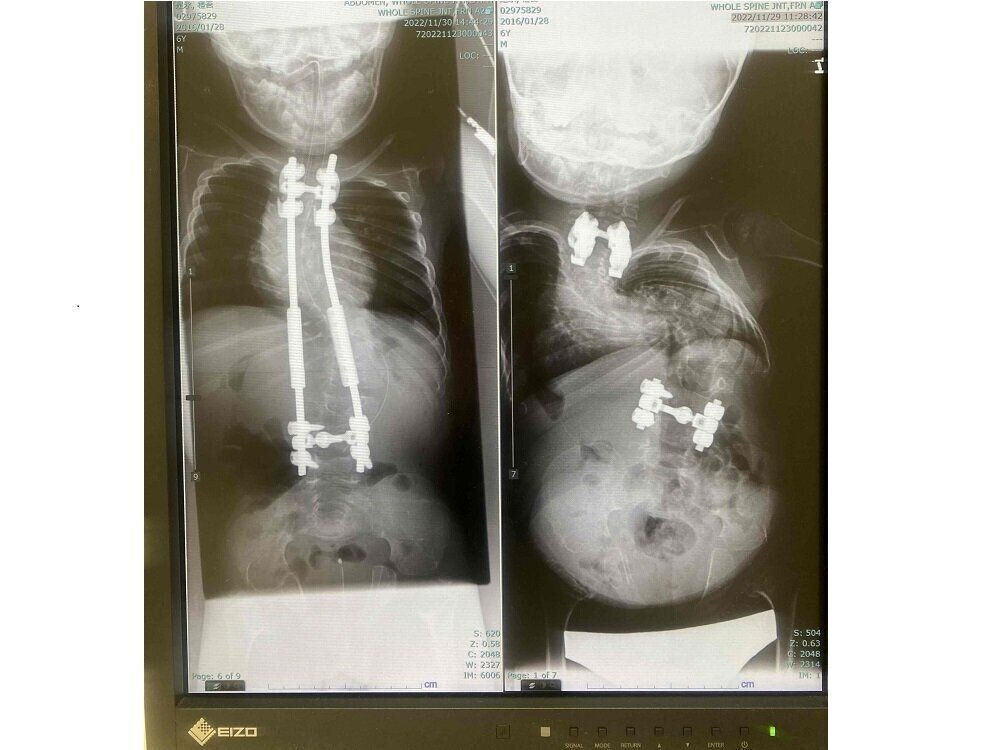

半年ごとに手術をして背骨を矯正。

橙吾くんは背骨が曲がる側弯症もあり、小学校1年生のときから半年に1回手術を受けています。

医師からは「進行が早いタイプで、ほうっておくと内臓が圧迫されて呼吸機能に影響するし、成長に伴い背中や腰などに痛みが出てくる」と言われています。そのため小学1年生のときから半年ごとにこども病院で手術を受けています。最初の手術で背中に金属棒を入れたときはゆがみがかなり矯正されて身長が7cmほど伸びました。その後は、半年に1回の手術で金属棒を少しずつ伸ばしていくのですが、1回の手術で身長は5mm~1cmぐらい伸びます。手術時間は2~3時間ぐらい。1週間ぐらい入院が必要です。

側弯症で背骨が曲がっていたときは縄跳びも跳べなかったのですが、背骨がまっすぐになってきたら縄跳びも跳べるようになりました。食べる量も増えてきました。身長も小学1年生では72cmだったのに、小学4年生の今では89㎝になりました。そうしたことひとつひとつが自信になっているようです。

橙吾くんのX線画像。側弯症の手術によって、体のゆがみが矯正されて、身長も伸びてきた。

脊椎の異常な彎曲(脊柱後側彎症および脊柱前彎症)は、小児期には重症化する傾向があります。そして頚椎(椎骨)の不安定もあり、脊髄損傷の危険性が増加します。また内反股や内反足などがあるため歩行がしにくいです。